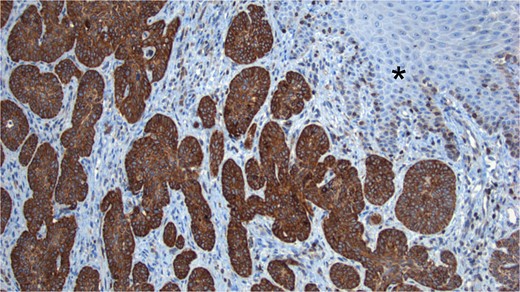

The sample was sent to pathology for consultation, where the provisional diagnosis was identified as ‘pigmented basaloid carcinoma.’ Microscopically, the hematoxylin and eosin-stained sections revealed a malignant tumor characterized by nests of cells with scant to moderate cytoplasm and basophilic nuclei, exhibiting peripheral nuclear palisading. Melanocytes and melanin pigment were observed within the tumor nests and stroma. Immunohistochemical tests showed positive results for p63 and CK5/6 (Fig. 1), and negative results for HMB-45. Additionally, intense and diffuse positivity for BCL2 was noted (Fig. 2). The final diagnosis confirmed a pigmented basal cell carcinoma with infiltrative, micronodular, and ulcerative patterns.

Hematoxylin and eosin (H&E) staining. (A) Display of normal stratified flat epithelium of the skin with a subjacent neoplasm featuring small nests. (B) Higher magnification reveals the tumor arising from the basal layer of the skin (*). The nests exhibit characteristic peripheral nuclear palisading (black arrows), and both melanin pigment and melanocytes are visible (white arrows). (C) Both the tumor and adjacent skin cells exhibit strong nuclear positivity for p63. (D) Tumor cells demonstrate strong positivity for high molecular weight cytokeratins (CK5/6).